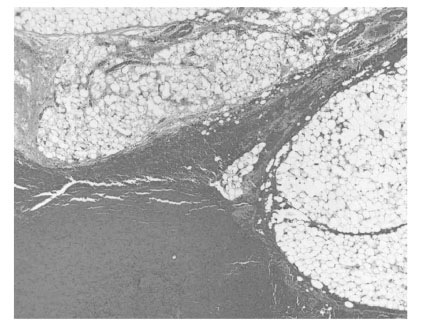

Fig. 3).

Fig. 3Microscopic findings showing hemorrhage of lipoma (H & E).